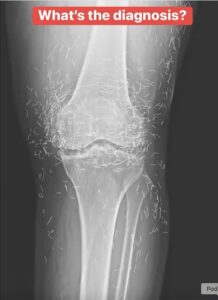

Her knee joint was filled with dozens of tiny gold needles, leaving everyone wondering how they got there and why they hadn’t been discovered sooner.

However, instead of using temporary needles, her acupuncturist had implanted fine gold ones beneath her skin permanently, believing they would release healing energy over time. This unusual practice was meant to provide continuous pain relief without repeated sessions.

Doctors explained that leaving metal objects inside the body can lead to serious complications. Permanent implants can cause inflammation, infection, or interfere with medical scans such as MRIs and X-rays.